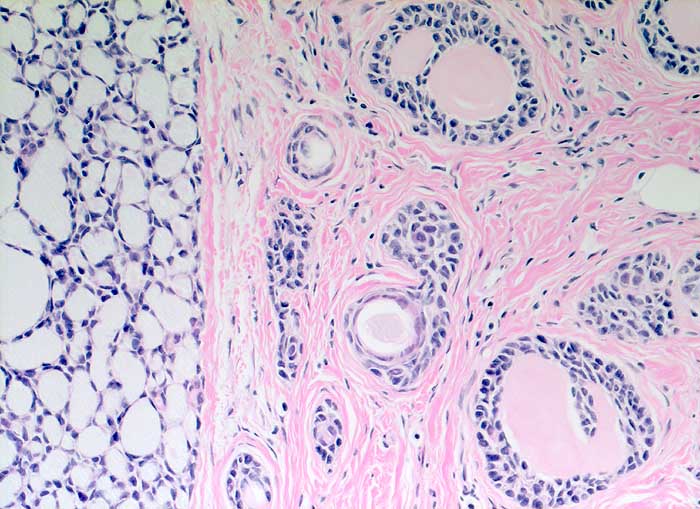

Adenoidzystisches Karzinom

Kribriforme Tumormasse. Die Hohlräume sind gefüllt mit mucoidem Material oder eosinophilem amorphem Material.

Adenoidzystische Karzinome kommen vor allem im Bereich der Speicheldrüsen vor, treten aber auch in anderen Organen auf. Sie machen weniger als 0.1% - 0.2% der Mammakarzinome aus.